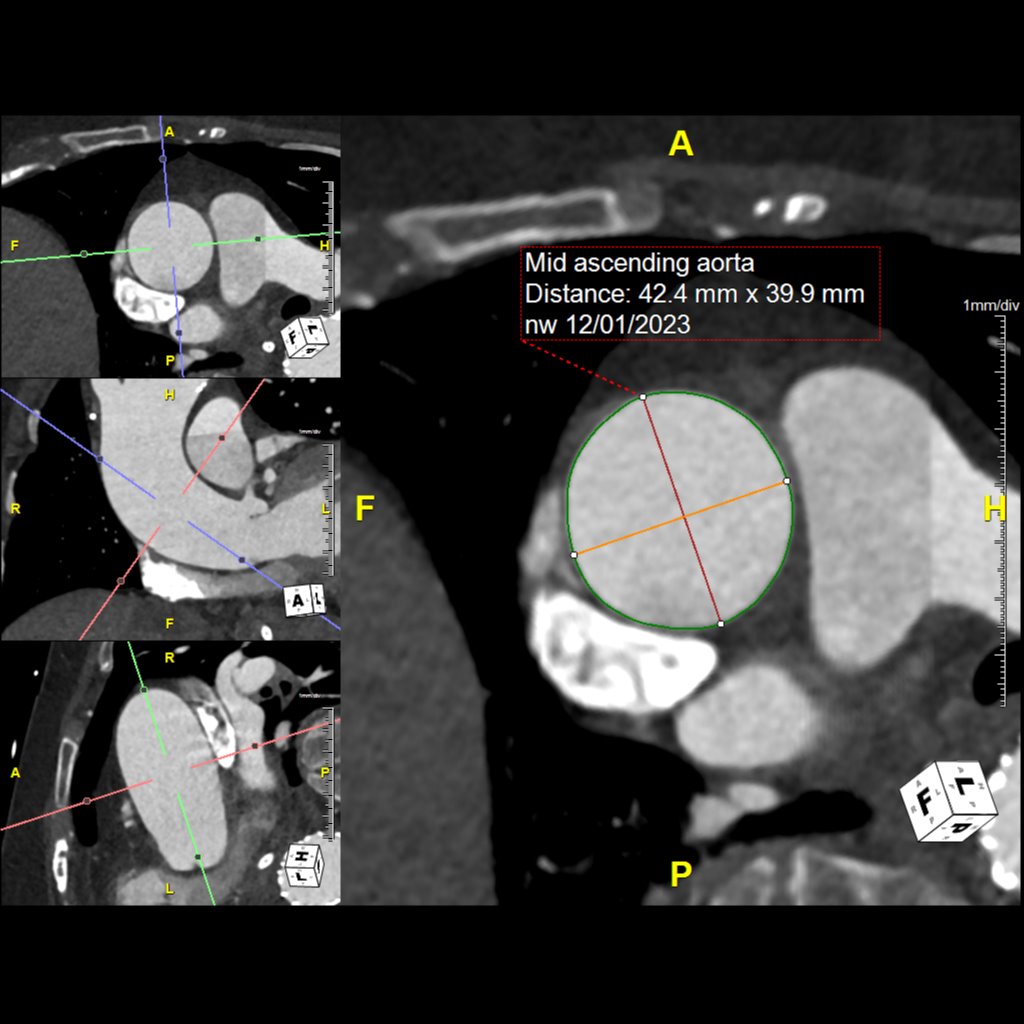

Our Post-Stent Service provides imaging for patients with stent placements in the abdominal aorta and common iliac arteries. The primary goal is to monitor changes in the maximum diameter of these vessels, ensuring early detection and management of post-stent issues. Using 3D imaging techniques identify critical aspects such as stent length, potential migration, and aortic diameter.

This protocol complements Routine Chest, Abdomen, and Pelvis imaging, offering an added layer of post-procedural monitoring. It allows quick viewing of major anatomy and focuses on identifying stent movement or aneurysm growth, ensuring comprehensive and effective monitoring.